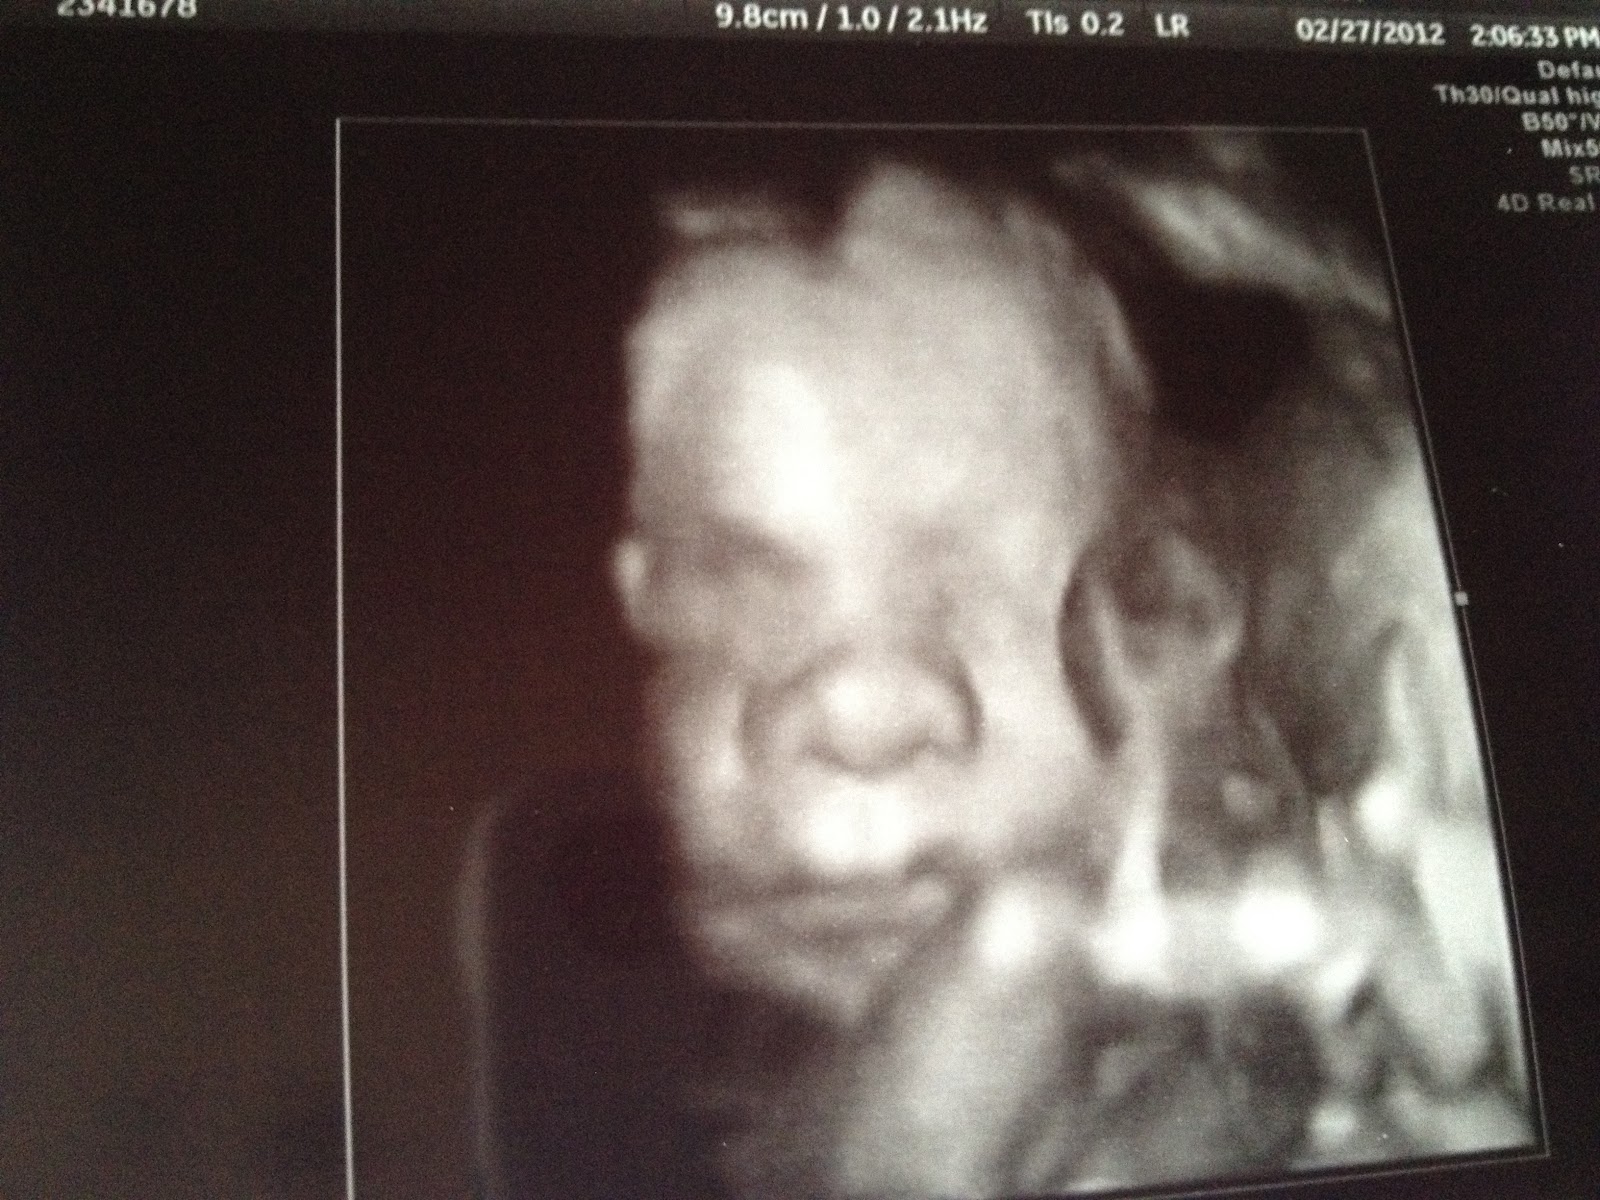

I just wanted to post a little update on J3.0. He is FABULOUS! Really, the doctors are amazed at how far we have made it with really no issues. We go every Monday for ultrasound to check up on this little guy. (I just have to say that I really appreciate good ultrasound technicians! For the tests we are doing, a good technician makes all the difference in the world!)

I am so thankful for the news update and glad that J3.0 is doing well so far. I love the ultra sound pics! It is amazing how far they come with technology! Will keep praying for you guys.